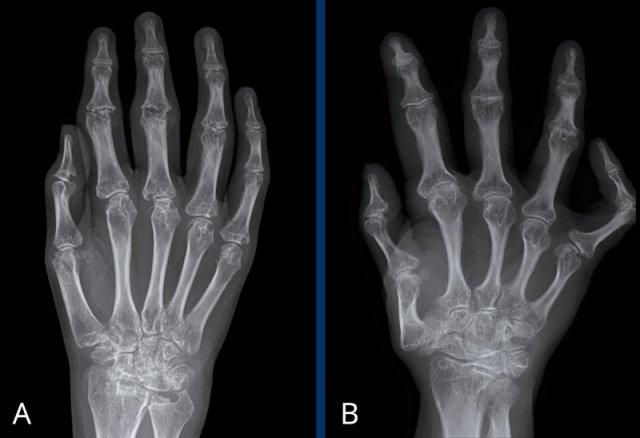

Hai bệnh nhân viêm khớp dạng thấp thiếu niên

A. Nhiều tổn thương bào mòn ảnh hưởng đến các xương cổ tay và khớp bàn ngón tay. Xẹp xương thuyền và xương nguyệt.

B. Bệnh nhân người lớn có tiền sử viêm khớp thiếu niên. Chiều dài xương bất thường do đóng sụn tăng trưởng sớm và phì đại đầu xương. Lệch trục khớp nặng.

Cả hai trường hợp đều có loãng xương quanh khớp.